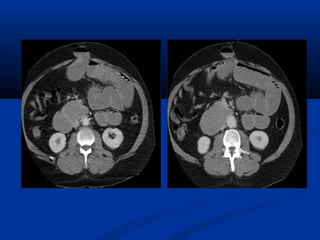

TRÒ SOÁ ÑAÄMÑOÄ Moãi phaân töû vaät (Voxel) coù trò soá töông öùng vôùi möùc ñoä haáp thu tia cuûa moâ vaø ñöôïc bieåu thò baèng caùc ñoä xaùm khaùc nhau treân hình ôû töøng phaân töû aûnh (pixel).

TRÒ SOÁ ÑAÄMÑOÄ Ñaäm ñoä cuûa nöôùc : 0 ñôn vò Hounsfield (HU) Ñaäm ñoä cuûa xöông :+ 1000 HU Ñaäm ñoä cuûa khí :–1000 HU Ñaäm ñoä môõ :–100 HU (ROI : Region Of Interest)

Một số mậtđộ (HU)Một số mật độ (HU)

Loaïi moâ Tròsoå chuaån (HU) Trò soá giôùi haïn (HU) Xöông ñaëc 250 >   Gan 65 +/– 5 45 – 75 Cô 45 +/– 5 35 – 50 Laùch 45 +/– 5 40 – 60 Haïch 45 +/– 10 25 – 55 Tuïy taïng 45 +/– 10 20 –40 Thaän 40 +/–10 Môõ - 65 +/–10   - 80 – - 100